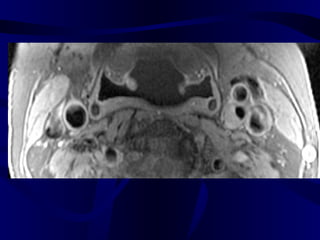

• 74.

Pre and Post-SPIOEnhanced Magnetic Resonance Imaging of ApoE K/O and Wild Type Mice: We used 4.7 tesla MRI unit in our study. After baseline MR imaging with respiratory gating, we injected 1mMolFe/kg super paramagnetic iron oxide to six ApoE deficient and two C57bl mice through the tail vein. Post-contrast MR imaging were performed in day 5 with the same parameters (TR=2.5 sec, TE=0.012 sec, FOV=6.6 cm, slice thickness=2.0mm, flip angle (orient)=trans, and matrices=256x256). We selected the aorta at the level of kidney for comparison of the baseline and post-contrast images.

Apo E deficientmice MRI SPIO experiment

MR Image ofAbdominal Aorta After SPIO Injection in Mouse Apo E deficient mouse C57B1 (control) mouse Before Injection After Injection (5 Days ) Dark (negatively enhanced) aortic wall, full of iron particles Bright aortic lumen and wall without negative enhancement and no significant number of iron particles